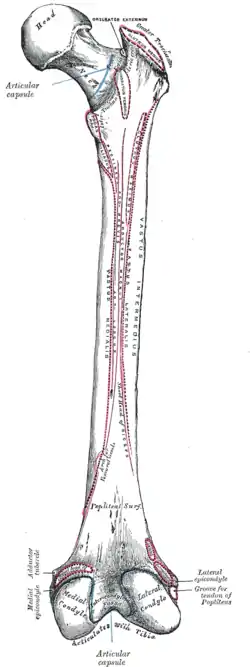

Right femur. Posterior surface. (Quadratus femoris labeled.) | |

Right femur. Posterior surface. (Quadratus femoris labeled at top center.) | |

Right femur. Posterior surface. (Quadratus femoris and Quadrate tubercle labeled.)

Right femur. Posterior surface. (Quadratus femoris and Quadrate tubercle labeled.)